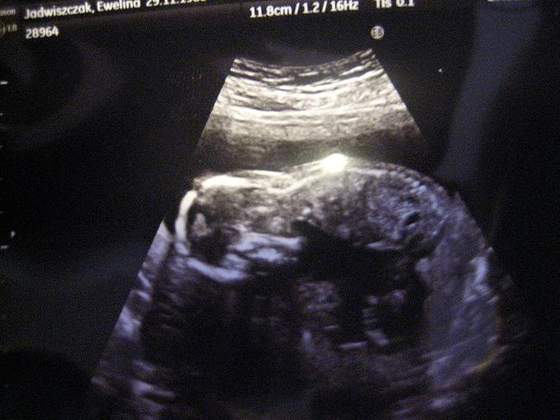

Dzisiaj bylam u lekarza :) kruszynka ma juz 12 cm :), i wszysko jest dobrze, dostalam tez magnez bo mam ostatnio skurcze lydek w nocy :( maluszek byl uparty i nie chcial pokazac co ma miedzy nozkami ;P